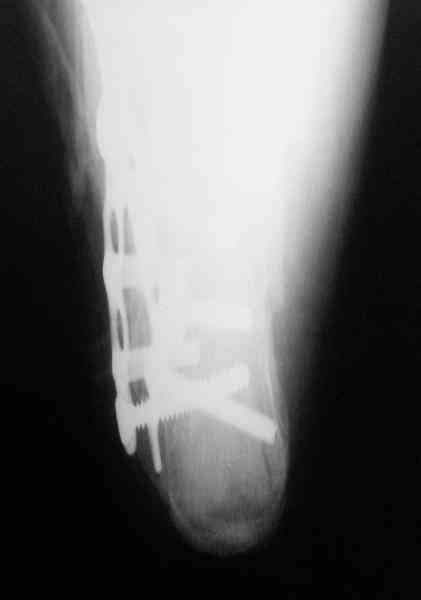

Re: Перелом пяточной кости

Пяточной пластиной

Открытый и закрытый способы лечения.